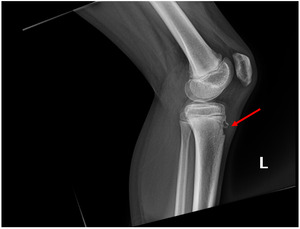

Osgood Schlatter disease (OSD) is characterized by pain at the tibia. Clinical symptoms include pain in the knee and trouble with mobility. Since OSD is often seen in growing kids who practice repetitive physical activities, it is commonly treated by applying ice on the knee, regularly stretching the knee, and limiting physical activity (Figure 3).